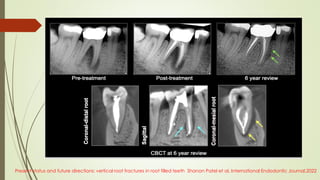

Present status and future directions: vertical root fractures in root filled teeth Shanon Patel et al, International Endodontic Journal,2022

Cone beam computed tomography (CBCT) overcomes the limitations of PRs by

providing undistorted images, which are not susceptible to anatomical noise and

enable the clinician to view the tooth from multiple planes and angles

(Durack & Patel, 2012).

 Results showed better sensitivity and specificity of CBCT scans

than PRs in the detection of VRFs in unfilled teeth, when a voxel

size of 0.2 mm was used.

• The sensitivity and specificity of VRF diagnosis in assessing gutta-percha filled canals were

32% and 68%

• The sensitivity and specificity of VRF diagnosis in assessing the empty canals (without

gutta-percha) were 72% and 96% .

• And concluded that intracanal filling materials such as gutta-percha reduce the diagnostic

ability of vertical root fractures. Hence, it is recommended to remove those materials from root

canals before imaging to improve the diagnostic potential of CBCT.